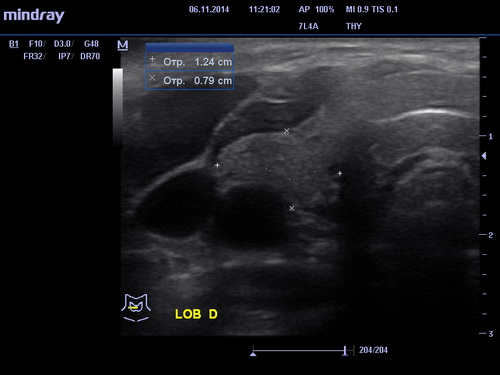

УЗИ щитовидной железы

ЗаписатьсяУЗИ представляет собой безопасное и надёжное исследование заболеваний щитовидной железы. В современном мире из-за плохой экологии, хронической нехватке йода эндокринные заболевания прогрессируют с небывалой скоростью. Для своевременного и быстрого реагирования на эти заболевания необходимо своевременно проходить обследования щитовидной железы.

УЗИ щитовидки полностью безопасная и безболезненная процедура. Врач, проводящий процедуру, предложит освободить шею и лечь на кушетку. Нанеся специальный гель на шею, он приступит к исследованиям. Осторожно двигая датчик вдоль шеи, стараясь лучше рассмотреть исследуемый орган, он зафиксирует все заметные изменения в нем. Небольшой датчик позволит прекрасно рассмотреть даже самые незначительные изменения.

Процедура занимает незначительное время. После нее нужно будет лишь убрать излишки геля с шеи. Квалифицированный специалист даст детальное письменное описание состояния исследованного органа.